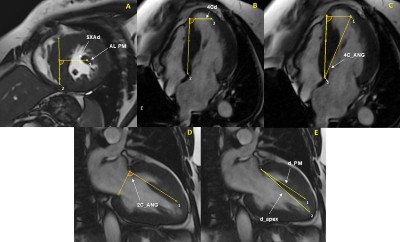

Methods: 143 patients with HCM (median age 58 (IQR 48-65) years, 64% male) who had undergone CMR were compared to 50 healthy controls (median age 32 (IQR 28-50) years, 40% male). The HCM cohort included 50 patients with non-obstructive HCM, 50 with obstructive HCM requiring transaortic myectomy, and 43 with obstructive HCM requiring transapical myectomy. Six independent measurements of PM anatomy were performed (Figure), comprising both established and novel measurements. Intergroup comparisons were made, and correlative analysis of PM measurements was performed using echocardiographic data and surgical outcomes.

There was significant variability in PM anatomy in all patients. The SXAd measurement was smaller (26.76 +/- 6.10 mm vs 32.10 +/- 4.85 mm, p < 0.001) in HCM patients versus controls. The 4Cd measurement was smaller in patients with apical HCM than in all other groups (p < 0.001). D_PM, d_apex, and the ratio between these measurements were consistent among all groups. No PM quantification in HCM patients correlated to pre-, intra-, or postoperative LVOT obstruction, NYHA class, or postoperative length of stay.